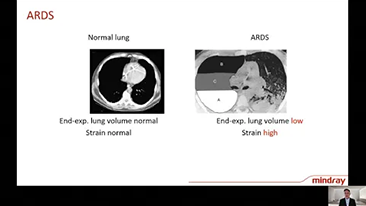

Choosing the correct ventilator settings for treating patients with respiratory tract disease is an important issue. Since the task of specifying the parameters of ventilation equipment is entirely carried out by a physician, their knowledge and experience in the selection of these settings has a direct effect on the accuracy of their decisions. There are numerous ventilation modes and decision-supporting tools which have been developed specifically to help caregivers improve efficiency and eliminate errors in clinical decision-making.